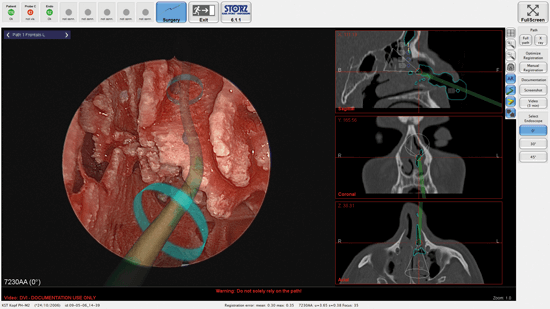

Figure 3. Augmented reality of preoperatively planned pathways to facilitate finding

the way to the frontal sinus. Courtesy of KARL STORZ Endoskope, Germany.

Computer-assisted navigation offers augmented reality tools to mark pathways for easier access to critical structures according to CT anatomy or mark them giving optical and/or acoustic feedback to the surgeon (see Figures 2 and 3). This can be especially helpful in an unclear surgical field. With the advent of stronger MRIs (>5 Tesla) tractography of white brain matter for example becomes more sensitive, and thus critical neurological deficits postoperatively can be avoided with better preoperative planning and intraoperative navigation [8].